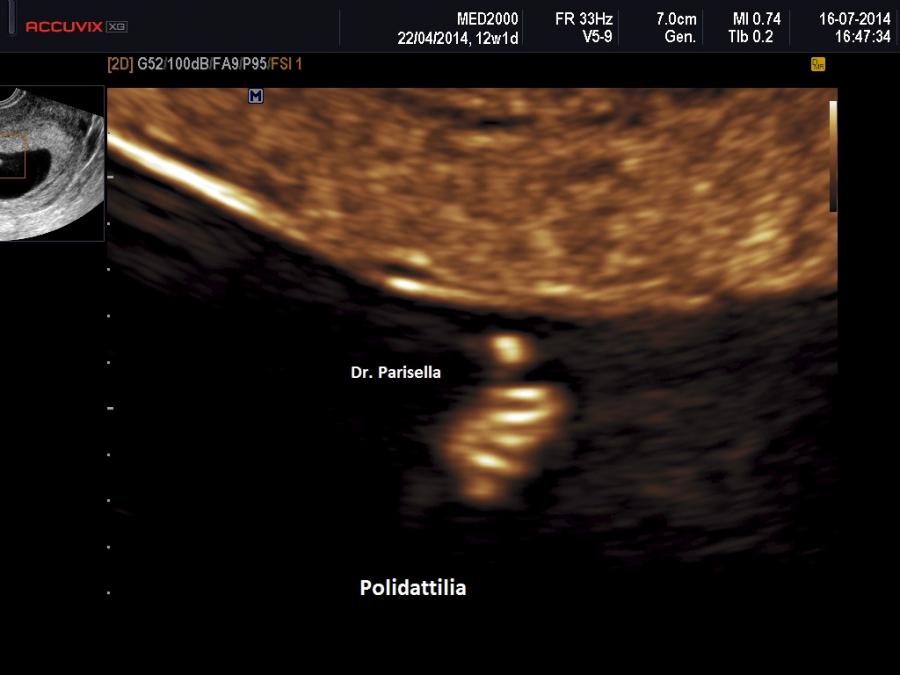

E' una malattia trasmessa con carattere autosomico recessivo caratterizzata da Polidattilia per lo più postassiale, Reni Policistici, Encefalocele Occipitale, Oligoamnios/Anidramnios in fase avanzata di gravidanza, Displasia Duttale Epatica.

La diagnosi ecografica prenatale si basa sulla triade: ENCEFALOCELE OCCIPITALE, POLIDATTILIA, RENI POLICISTICI.

I tre tipi, a diversa espressione genetica, hanno diversa espressione fenotipica. La polidattilia frequente in MKS1 è rara in MKS3. La MKS1 ha anche una variante campomelica.